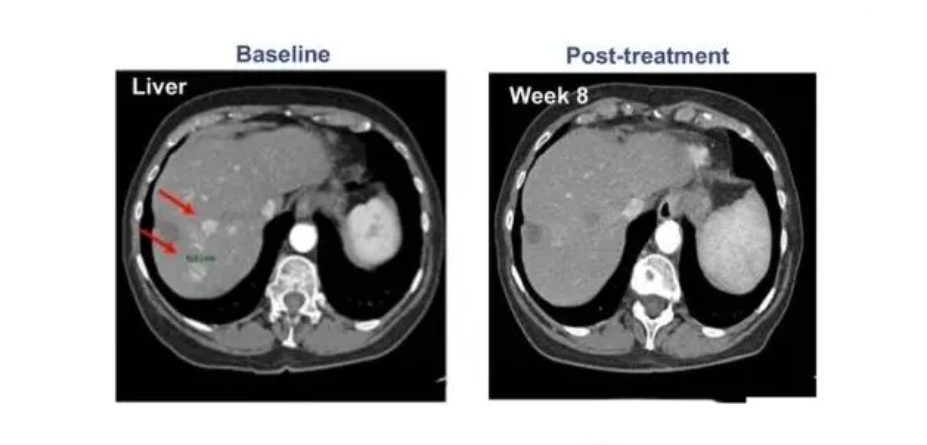

2022年5月9日,SCG101自體T細胞注射液獲得新加坡藥監(jiān)局(HSA)的臨床試驗批準。而在3月10日,國家藥品監(jiān)督管理局藥品審評中心(CDE)公示顯示,SCG101自體T細胞注射液成功獲得臨床試驗?zāi)驹S可,用于治療乙型肝炎病毒(HBV)相關(guān)的肝細胞癌(HCC)。

此前,在2020年國際肝病大會(ILC)上,一款基于T細胞的肝癌新型TCR-T療法ADP-A2AFP引起了不小的轟動,在納入的患者中,有一名患者的癌細胞進程出現(xiàn)了完全緩解,其余參與者的甲胎蛋白(AFP)也都出現(xiàn)了不同程度的下降,這意味著試驗取得了進展,也說明該療法針對晚期肝癌的治療是有效果的。